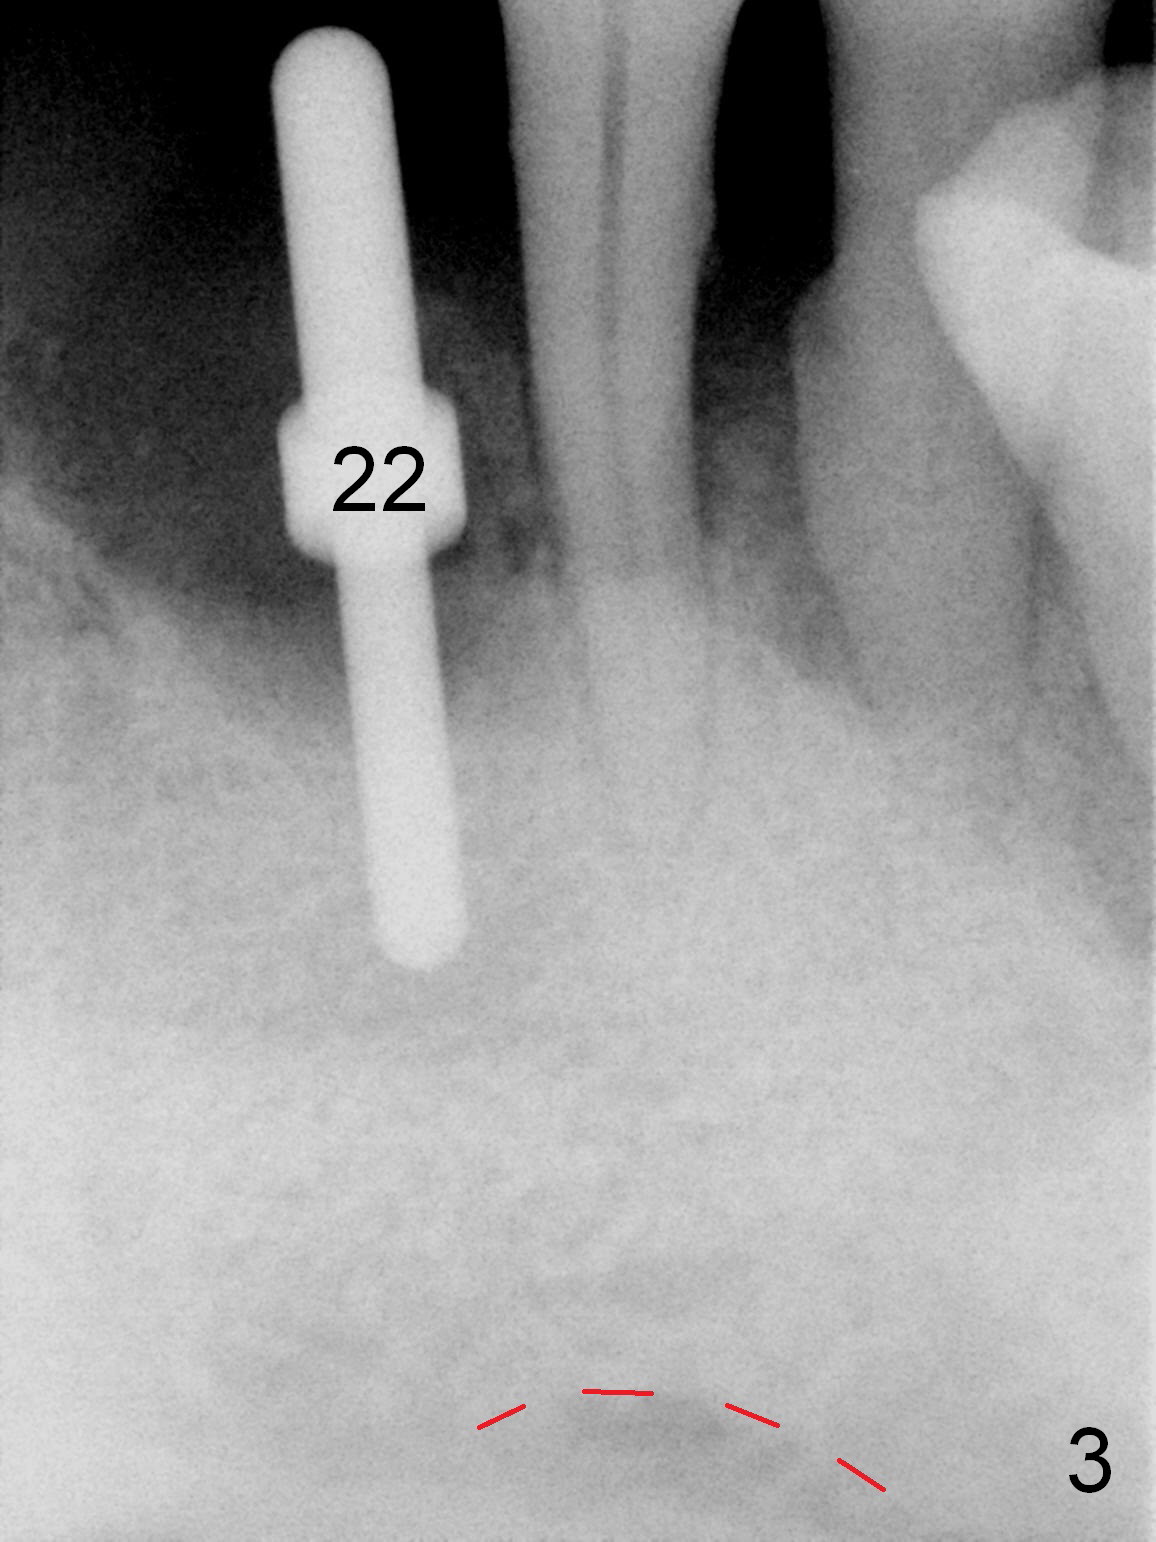

As expected, the bone density in the mandibular anterior region is found to be high during initial osteotomy (Fig.1-3). Five implants are placed at the sites between #22 and 28 (Fig.4,5): 3x14(2) mm 1-piece (bone-level) implants in the incisor region; 4.5x17 mm 2-piece (tissue-level) ones in the canine/premolar area. All of the implants are placed as lingual as possible. Bone graft is placed (*). Red dashed line: the superior border of the Inferior Alveolar Canal. Immediate splinted provisional bridge is fabricated. One week postop, periodontal dressing remains attached to the provisional and the gingiva.